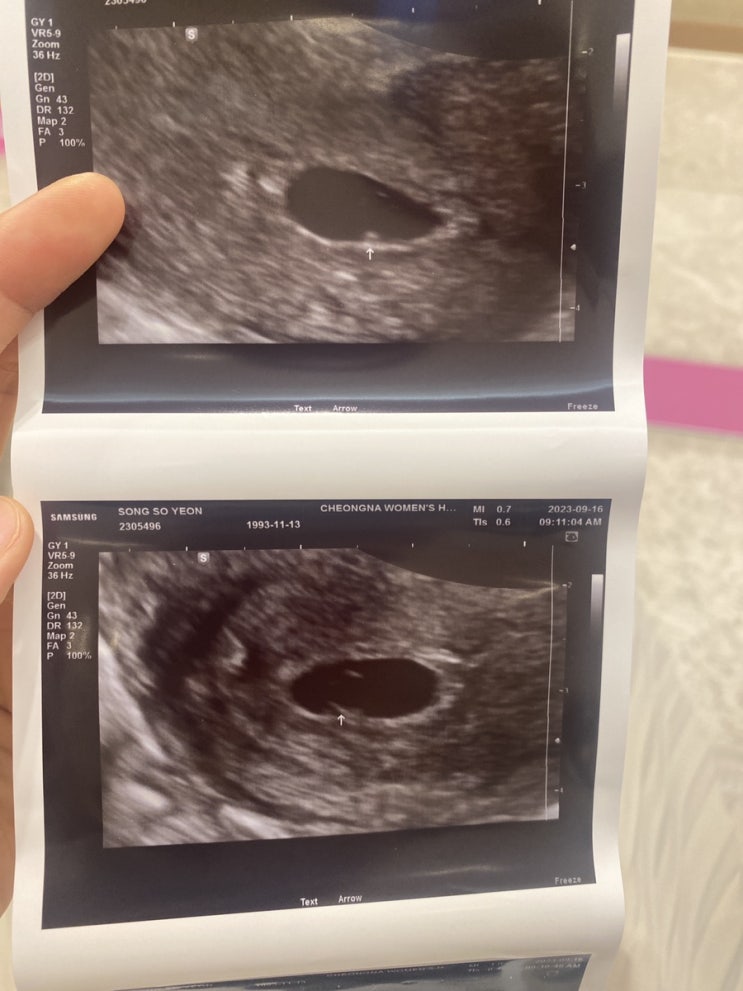

다솜이 첫만남

9/16일 첫만남 한번의 유산 다시 만난 소중한 아가 아프지말고 건강하게만 태어나다오 “애틋하게 사랑하는...